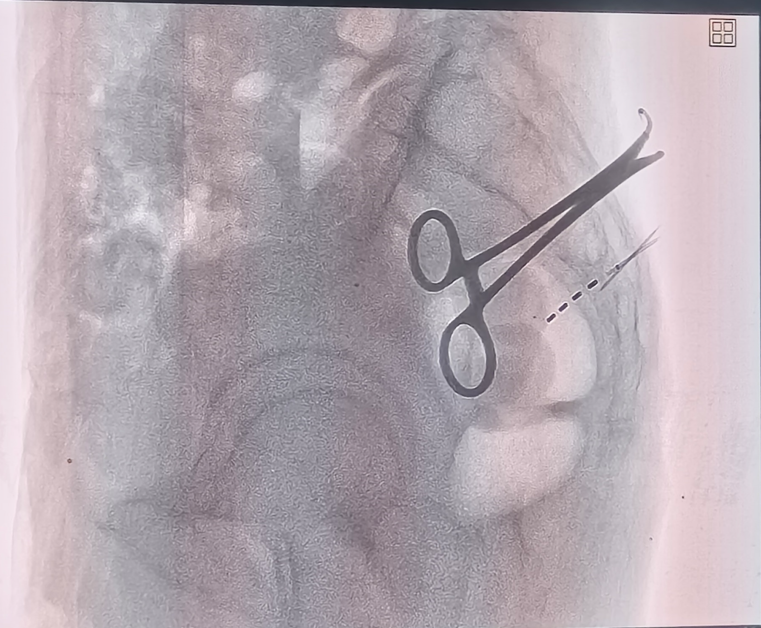

考虑到李爷爷高龄、病情复杂,郑学胜团队量身定制了骶神经调节术方案。该手术通过微创方式植入电极,精准调节骶神经功能,恢复肠道正常蠕动节律。

骶神经电极植入

术后仅两天,李爷爷就恢复自主排便,骶尾部疼痛显著缓解,目前已顺利出院。